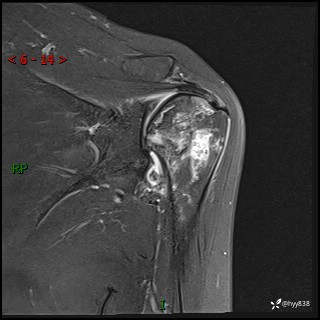

现病史:患者1月前无明显诱因出现左肩关节疼痛,于2024.07.31就诊于我院骨科门诊完善左肩关节MR:左肱骨头信号异常,肿瘤?建议进一步检查。左肩关节积液。左腋窝淋巴结增大。今为求明确诊断就诊我科,门诊以“骨质破坏”收入我科。 起病以来,精神食欲睡眠尚可,大小便正常,体力体重无明显变化。

肱骨MRI平扫(axi T1WI+cor T2WI-fs)+CE-fs(COR+SAG)